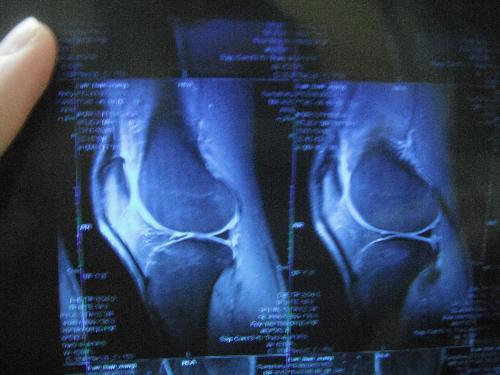

滑膜炎

滑膜炎常识

关节滑膜炎要如何保护预防

滑膜一旦遭受了打击的时候,会导致患者的身体出现明显的病变,有的甚至会导致患者的关节出现病变,引发炎症。而且,膝盖是人体的重要关节部位,其遭受了损伤的时候,会导致人体的关节腔产生积液,出现病损 。那么,患者要如何对这种疾病